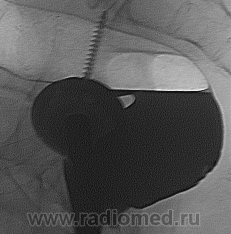

Ой, ещё один снимок не выложил:

Да, последний снимок тоже показателен.

В данном случае большую роль сыграли онколог с пальцевым исследованием прямой кишки и эндоскопист с взятием биоптата, так что от меня только формальность-в последнюю очередь. По поводу красной стрелки это пузырьки газа с отграничением контраста, а то что указано стрелкой скорее всего остаточная перистальтика, на остальных снимках нет чего такого подобного, да и под скопией такое очень заметно.

С пузырьками газа можно согласиться, я их «до кучи» обвёл, хотя по этой миниатюре…, но у Вас были нормальные снимки. А вот перистальтика, с такой крутизной и углами… непохоже.

Нет, на №9 это место не видно, №1 ближе, но тоже не то. Огромная просьба: покрупнее репродукции делать. Не пойму, почему некоторые снимки у Вас получаются двухконтурными… какое-то сотрясение в поперечном направлении? Например, особенно заметно на №1, №2 №4, №6. Это явно не из-за длины выдержки. Может быть электромеханику, который аппарат обслуживает, показать снимки, что-то разболталось?